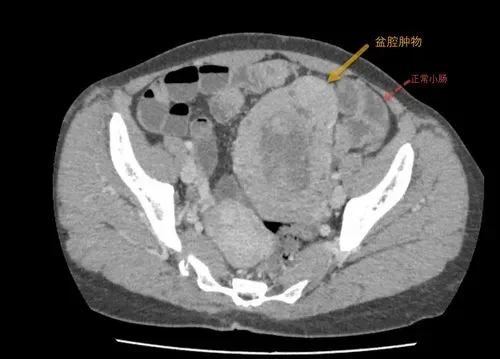

小肠间质瘤的诊断是一个复杂过程,需要结合临床信息、辅助检查结果及医生经验做出诊断。大量文献表明,影像学检查如CT或MRI在诊断GIST方面起到关键作用。

其次,影像学检查是确诊GIST的重要手段。CT扫描可以显示肿瘤的大小、形态以及与周围组织的关系,而MRI则有助于进一步评估肿瘤的侵袭性。